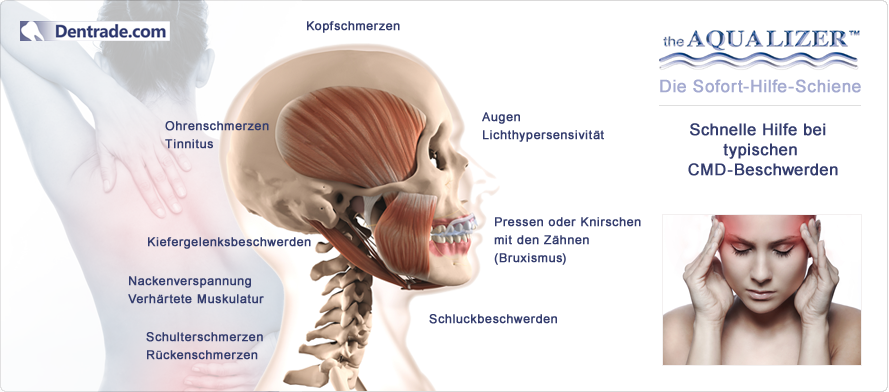

AQUALIZER™ - (аква+еквілібрація) - це наповнена водою накусочна шина, яка функціонує за гідростатичним принципом

• усуває болі в м’язах за допомогою еквілібрації та релаксації

Завдяки водяному наповненню аквалайзер автоматично пристосовується до анатомічних особливостей пацієнта. Аквалайзер також добре зарекомендував себе при анамнезі та клінічній функціональній діагностиці як засіб діагностики та тимчасовий (лікувальний) засіб. Аквалайзер моментально компенсує неправильний прикус та встановлює збалансовану нервово-м`язову позицію нижньої щелепи. Позиція щелепи, при якій м`язи розслаблені, досягається за декілька хвилин. Для виготовлення нервово-м`язевого регістрату рекомендується тривалість носіння 1-2 тижні. За допомогою оклюзійних відбитків на пластмасовій поверхні аквалайзера візуалізується надмірний тиск при накусуванні чи скреготанні. Гідростатичний ефект також проявляється при застосуванні аквалайзера одночасно з іншою шиною.

Замкнена рідинна система аквалайзера діє динамічно та постійно, щоб збалансувати обидві сторони щелепи. Нижня щелепа завжди встановлюється в оптимальну позицію. Аквалайзер функціонує за гідростатичним принципом, який вперше було описано фізиком Паскалем. Згідно цього принципу, в замкненій рідинній системі тиск розподіляється рівномірно в усіх напрямках. Аквалайзер ідеально використовує цей принцип як саморегулююча шина. При цьому всі оклюзійні сили спрямовуються симетрично відносно осі, таким чином виникає стабільна оклюзія. Зуби просто можуть ковзати по гнучкій та гладкій поверхні прикусної подушечки аквалайзера. Гнучкі подушечки між обома оклюзійними поверхнями аквалайзера виключають усі контакти “зуб-до-зуба”. Функції пропріорецепторів зубів, м`язів та щелепних суглобів нейтралізуються. Звичайна, керована пропріорецепторами оклюзія усувається. Нижня щелепа, з допомогою розслаблених м`язів, може рухатися в комфортну позицію. Вже за декілька хвилин нова, розслаблена позиція усуває примусову болючу звичайну оклюзію пацієнта. В пацієнтів з хронічними болями цей процес триває трошки довше.

Просте застосування аквалайзера спричиняє нервово-м`язову оклюзію, що виключає будь-які оклюзійні інтерференції в статиці та динаміці. Таким чином запобігається статичному впливові неправильної (помилкової) оклюції. Нижня щелепа автоматично стає в збалансовану м`язову (керовану м`язами) позицію. Жувальні сили, а також аксіальні (осьові) зсуви в нижній щелепі компенсуються.